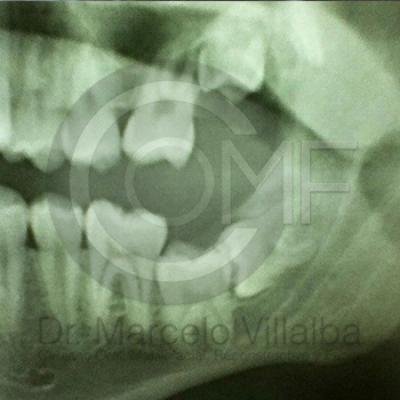

Generalmente en el momento de su erupción presentan procesos inflamatorios en la zona posterior de la cavidad oral, infección, dolor, movilidad de órganos dentarios, mal sabor en boca, mal olor en boca (halitosis), infección, incluso edema (aumento de volumen en tejido blando de la cara y/o boca) y complicaciones si no son atendidos. En el apoyo de diagnóstico se pueden requerir radiografías panorámicas y hasta tomografía en caso de ser necesarios.

Para el tratamiento de estas patologías se necesita en forma inicial estudios de laboratorio, radiografías o tomografías, estos estudios serán solicitados por el especialista a cada caso en particular, siendo su tratamiento quirúrgico bajo la modalidad de anestesia local o anestesia local más sedación consciente se puede realizar el procedimiento en corto tiempo y buen pronóstico.